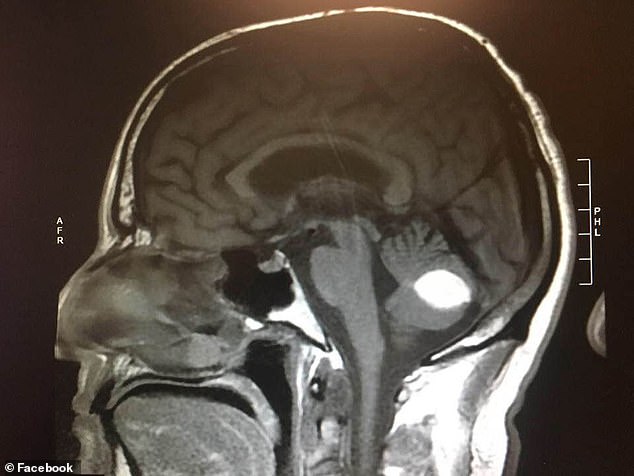

几个月前,伍德先生时常头痛欲裂,病发时不得不扶着墙壁走路。于是,他去医院做了检查。医生们给出了不同的诊断结果: 一名加州大学旧金山分校的神经外科医生认为他患有颅内出血;另一名放射科医生认为他脑部有肿瘤。

然而,就在做手术的前一天,伍德先生被告知手术取消了。其原因是:术前的X光片显示,他的脑部已无任何异常。